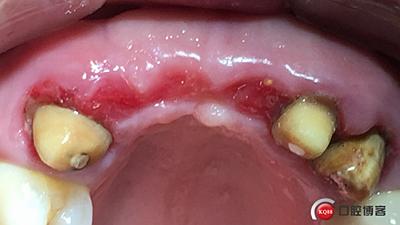

患者女性,52歲,缺失三顆牙,骨性前突,頜弓窄,身高175,魁梧,放了三顆牙是不是有點細?左上3開膠了,牙體有腐蝕。

設(shè)計:1.僅做牙槽嵴頂水平切口,不做垂直切口,2.缺牙區(qū)由三顆牙改成兩顆牙,3.鄰牙冠延長。

水平切口,鄰牙冠延長。